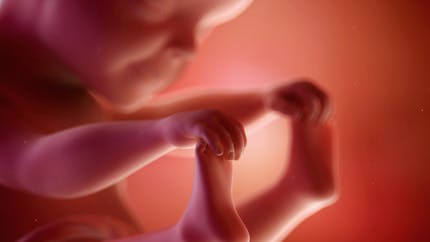

21ème semaine de grossesse (23 SA) Malgré les nombreux changements subis par votre organisme, vous vous sentirez bien mieux lors de votre 21ème semaine de grossesse (=23ème semaine d'aménorrhée) Profitez de ces moments Bébé suce désormais souvent son pouce et peut entendre les bruits, en particulier les sons gravesSupa za bebe sa brokolijem Ako tražiš recepte za supe za bebe sa brokolijem, na pravom si sajtu Pogledaj ovih 23 recepta iz kategorije supa za bebe sa lors de la 23ème semaine d'aménorrhée ou 21ème semaine de grossesse, la peau de votre bébé est encore si translucide qu'on pourrait y voir au travers à partir de maintenant et alors que le cinquième mois de la grossesse arrive, le poids du fœtus va augmenter considérablement chaque semaine et vous le sentirez de plus en plus bouger dans votre

Vous êtes toujours dans votre cinquième mois de grossesse 21 semaines de grossesse ou 23 SA votre corps, enceinte Fatigue En ce cinquième mois de grossesse, votre bébé commence à puiser dans vos réserves en fer Vous risquez donc d'être sujette à une carence si vous n'y prenez pas garde L e premier symptôme est une fatigue importante23 Klikni za više informacija o 23 nedelji 24 Klikni za više informacija o 24 nedelji Unesite termin porodjaja ili datum rodjnja vase bebe i pratite njegov razvoj iz nedelje u nedelju Registruj se Popularni alati Sa unapred pripremljenom torbom, odlazak u porodilište će biti oslobođen stresa